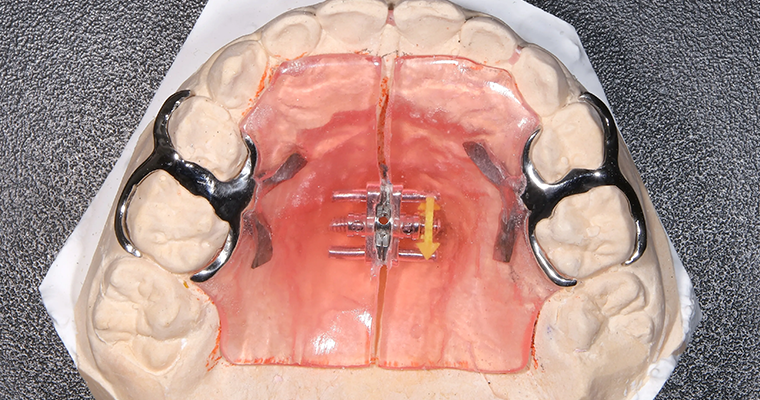

使用矯正装置 上

使用矯正装置 下

拡大床矯正(Rapid Maxillary Expansion、RME)は、上顎骨(口蓋骨)を広げるための小児矯正治療法の一つです。主な目的は、上顎の幅を広げ、歯列の不正咬合や呼吸障害を改善することです。

メカニズム

RME治療では、特殊な装置を使用して上顎の骨を広げます。この装置は、上顎の両側にある歯に取り付けられ、ねじを回すことで上顎の幅を徐々に拡大していきます。この過程で、上顎の中隔(鼻と口腔を仕切る部分)や歯槽骨が広がり、上顎骨の幅が拡大します。

適応年齢

RME治療の適応年齢は、通常、乳歯から永久歯に生え変わる時期である6歳から9歳くらいの間です。この時期に上顎の成長が終了していないため、上顎骨を広げることが比較的容易です。治療の適切な時期は歯科医が判断し、必要に応じて治療計画を立てます。

治療期間

RME治療の期間は個々の症例によって異なりますが、通常は6〜8ヶ月です。装置を毎日少しずつねじることで上顎骨が拡大され、治療が進行します。その後、骨が十分に広がった後も、安定するまでの期間があります。

治療終了後は、通常はリテーナーなどの装置を使用して結果を維持します。RME治療は、歯列の不正咬合や呼吸障害、口蓋裂などの症例に有効であり、適切な時期に行うことで効果的な治療結果を得ることができます。